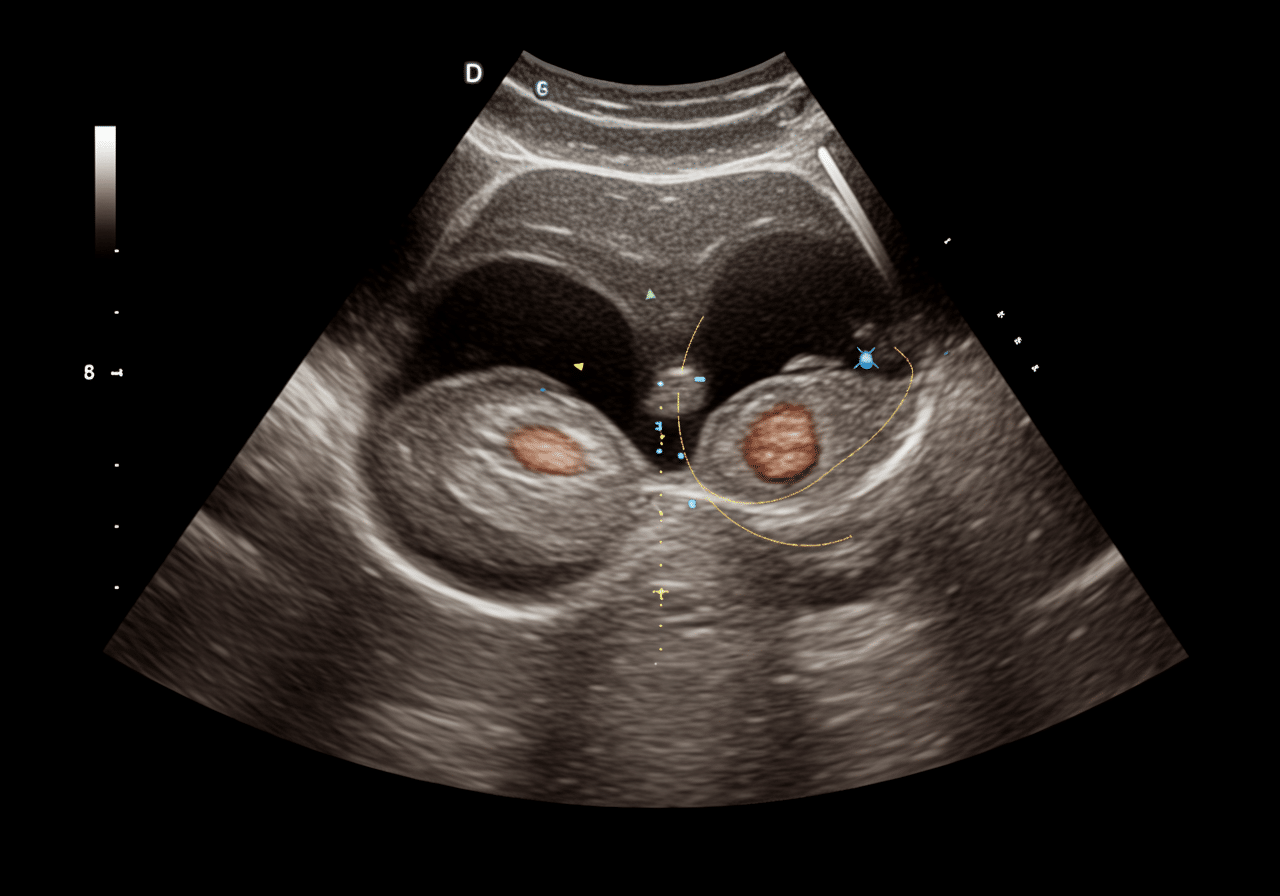

Priority ER's diagnostic capabilities for pelvic ultrasound for ectopic pregnancy or ovarian torsion exceed Joint Commission standards for emergency departments[14], featuring high-resolution transvaginal ultrasound probes (5-9 MHz) enabling visualization of gestational sac at β-hCG 1500-2000 mIU/mL (discriminatory zone), identification of yolk sac and fetal pole confirming intrauterine pregnancy excluding ectopic diagnosis, and color Doppler assessment detecting ovarian blood flow (present: rules out torsion; absent: confirms torsion) with 92% sensitivity when clinical suspicion high. Our emergency physicians trained in emergency ultrasound perform systematic evaluation including visualization of adnexa identifying ectopic mass with "ring of fire" vascular sign (90% specific for ectopic), assessment for free fluid in Morrison's pouch and pelvis indicating hemoperitoneum from rupture, and ovarian Doppler demonstrating whirlpool sign (twisted vascular pedicle) pathognomonic for torsion[15]. The integration of quantitative β-hCG correlation with ultrasound findings determines next steps: IUP visualized (excludes ectopic), β-hCG >discriminatory zone without IUP (presumed ectopic), or β-hCG below discriminatory zone (follow-up in 48 hours assessing doubling).

Advanced assessment through our comprehensive diagnostic capabilities provides progesterone level measurement (>25 ng/mL suggests viable IUP, <5 ng/mL suggests nonviable), serial β-hCG monitoring determining appropriate rise (normal: doubles every 48-72 hours in early pregnancy), and diagnostic dilation and curettage when β-hCG plateau suggests nonviable pregnancy but location uncertain. For ovarian torsion evaluation, our emergency physicians assess ovarian size (normal: 3-4 cm; >5 cm increases torsion risk), identify dermoid cyst or other masses predisposing to torsion, and evaluate uterine Doppler distinguishing torsion from pelvic inflammatory disease or appendicitis presenting similarly. This comprehensive approach explains why the American College of Obstetricians and Gynecologists mandates transvaginal ultrasound as gold standard for suspected ectopic pregnancy, providing definitive visualization of gestational location determining whether methotrexate medical management versus surgical intervention required preserving fertility while preventing life-threatening rupture.